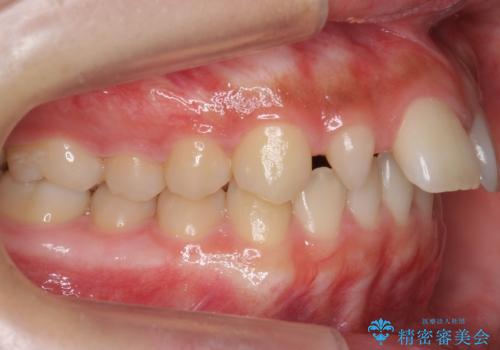

- 前歯の並びを主訴に来院。

前歯が出ており、また、左上の側切歯が1本生まれつき少ない状態でした。

また、右の奥歯の関係も上が前にある状態で大きくずれていました。

臼歯関係は無理に1級にしようとすると抜歯が必要になります。

今回は左右とも1歯対2歯の関係であるため、それは変えずに前歯を可及的にひっこめて足りない部分をブリッジで補う治療としました。

奥歯の関係を完全に1級にするには右上の小臼歯の抜歯が必要でしたが、もともと左上の前歯が生まれつき少ないため今回は歯を抜かずに治療しています。